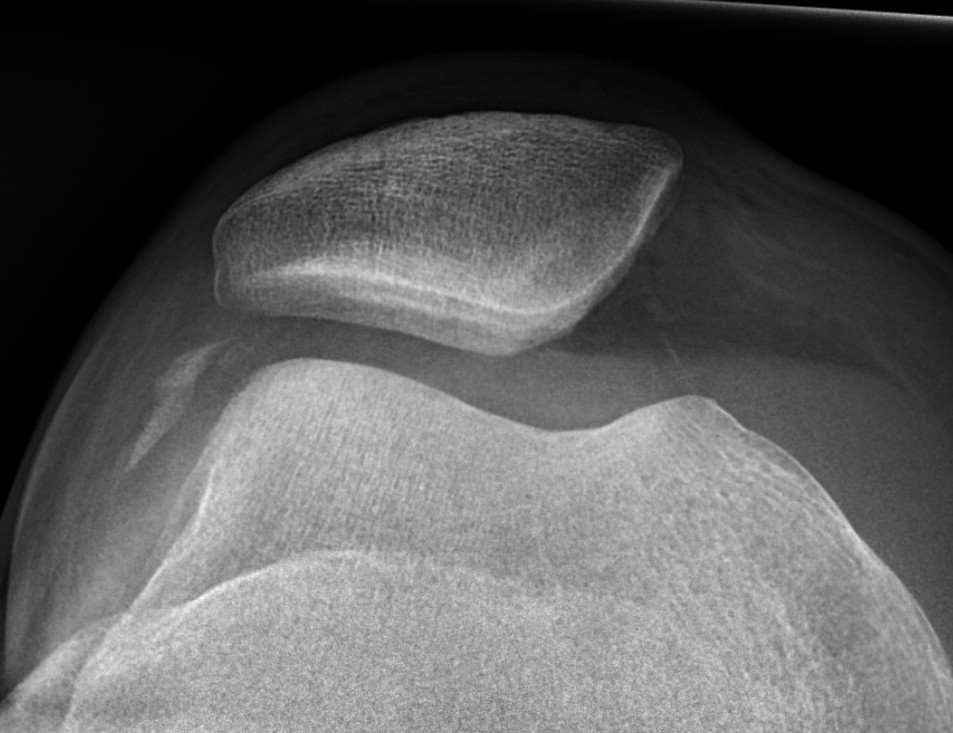

Xray

Look for osteochondral fractures

- skyline xray: suprapatella pouch

Osteochondral fracture visible on skyline view